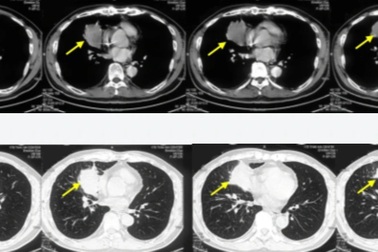

Bỗng dưng khó thở, tức ngực, phát hiện ung thư phổi di cănNgười phụ nữ được đưa đến bệnh viện sau vài ngày uống thuốc điều trị khó thở, tức ngực. Bác sĩ phát hiện bệnh nhân tràn dịch ngoài màng tim, có dấu hiệu ung thư biểu mô tuyến của phổi di căn.

Ho khan, tức ngực 10 ngày, vào viện đã ung thư phổi giai đoạn muộnNgười đàn ông 62 tuổi vào viện khám với biểu hiện đau tức ngực, ho khan. Bác sĩ phát hiện ông có khối u ở phổi phải.

Khó thở, tức ngực đi khám, người phụ nữ phát hiện ung thư phổi di cănSau hơn một tháng có biểu hiện khó thở, ho khan kèm theo đau tức ngực, đau nhiều cột sống cổ, người phụ nữ 56 tuổi (Bắc Kạn) đi khám thì phát hiện mắc ung thư phổi giai đoạn muộn, đã di căn xương-gan.